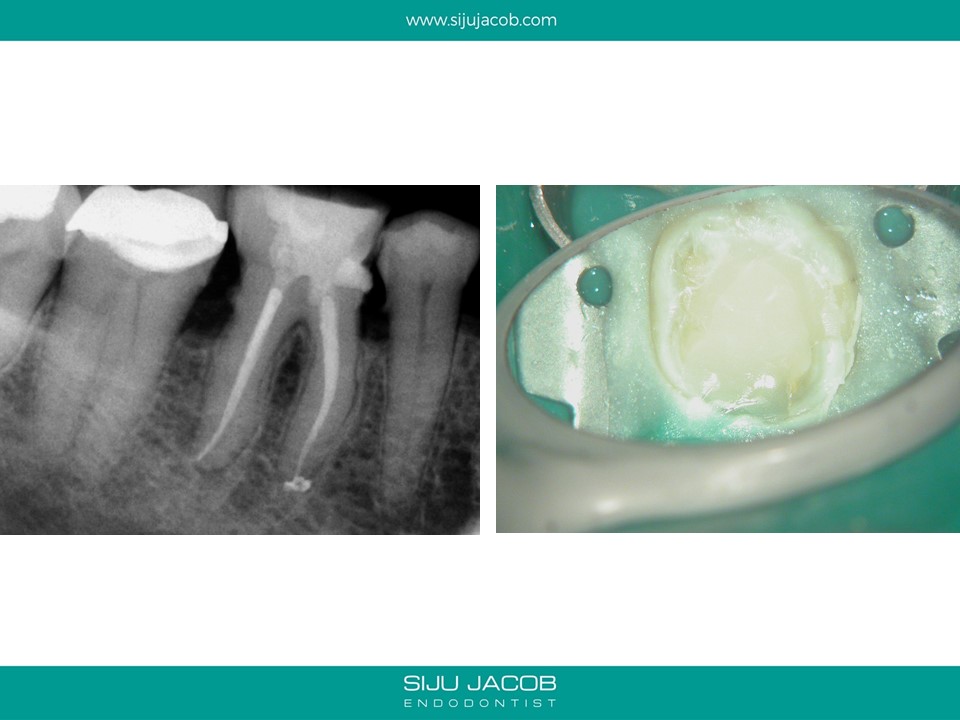

This case illustrates two things.

1) When examining for calcified canals, I like to put some EDTA, scrub the chamber and then examine under the microscope for clues. A cleaner floor is easier for color differentiation.

2) Specially in posterior teeth, canals tend to calcify and appear as “white spots”